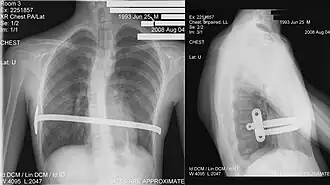

В ходе операции производится два небольших боковых разреза с обеих сторон грудной клетки. Через отверстие вводят интродьюсер, который проводят сначала в подкожное пространство, под мышцы, внутрь грудной клетки и за грудину, далее проводится перед перикардом в сторону противоположному разрезу кожи. Процесс можно контролировать с помощью торакоскопа. К интродьюсеру фиксируют тесьму и производят извлечение интродьюсера. По ленте вдоль сформированного канала проводится специальная титановая или стальная пластина (обычно её вводят с правой половины грудной клетки). Когда пластина введена и корректно размещена, её поворачивают. Заключительный этап операции — фиксация и стабилизация пластины — это делается нескольким способами — подшиванием к ребрам и мышцам, установлением специальных фиксаторов (по Парку) или с использованием стабилизаторов (классически по Нассу или по Пилегарду).